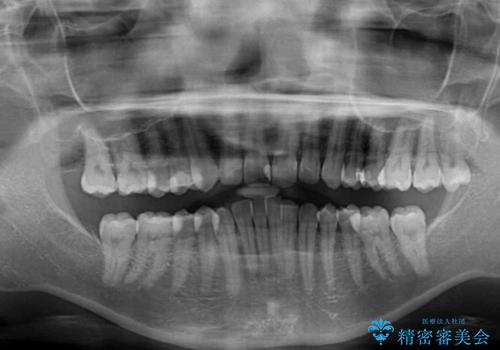

沖縄から飛行機で通院 インビザラインによる矯正治療

- 30代女性

- インビザライン

- 3年8ヶ月

- 定期的に東京に来るので、沖縄から矯正治療で通院したいとのことで来院された患者様です。

歯列不正は軽度であったので、応急処置の少ないインビザラインにて矯正治療を行うこととしました。

通院途中に、仕事の都合で東京に来る機会が激減してしまったため、なかなか治療が進まず、当初終了予定であった時期が2年近くずれ込んでしまいました。

今後もむし歯治療が必要となるため、日程を調整して沖縄から通院されるとのことでした。